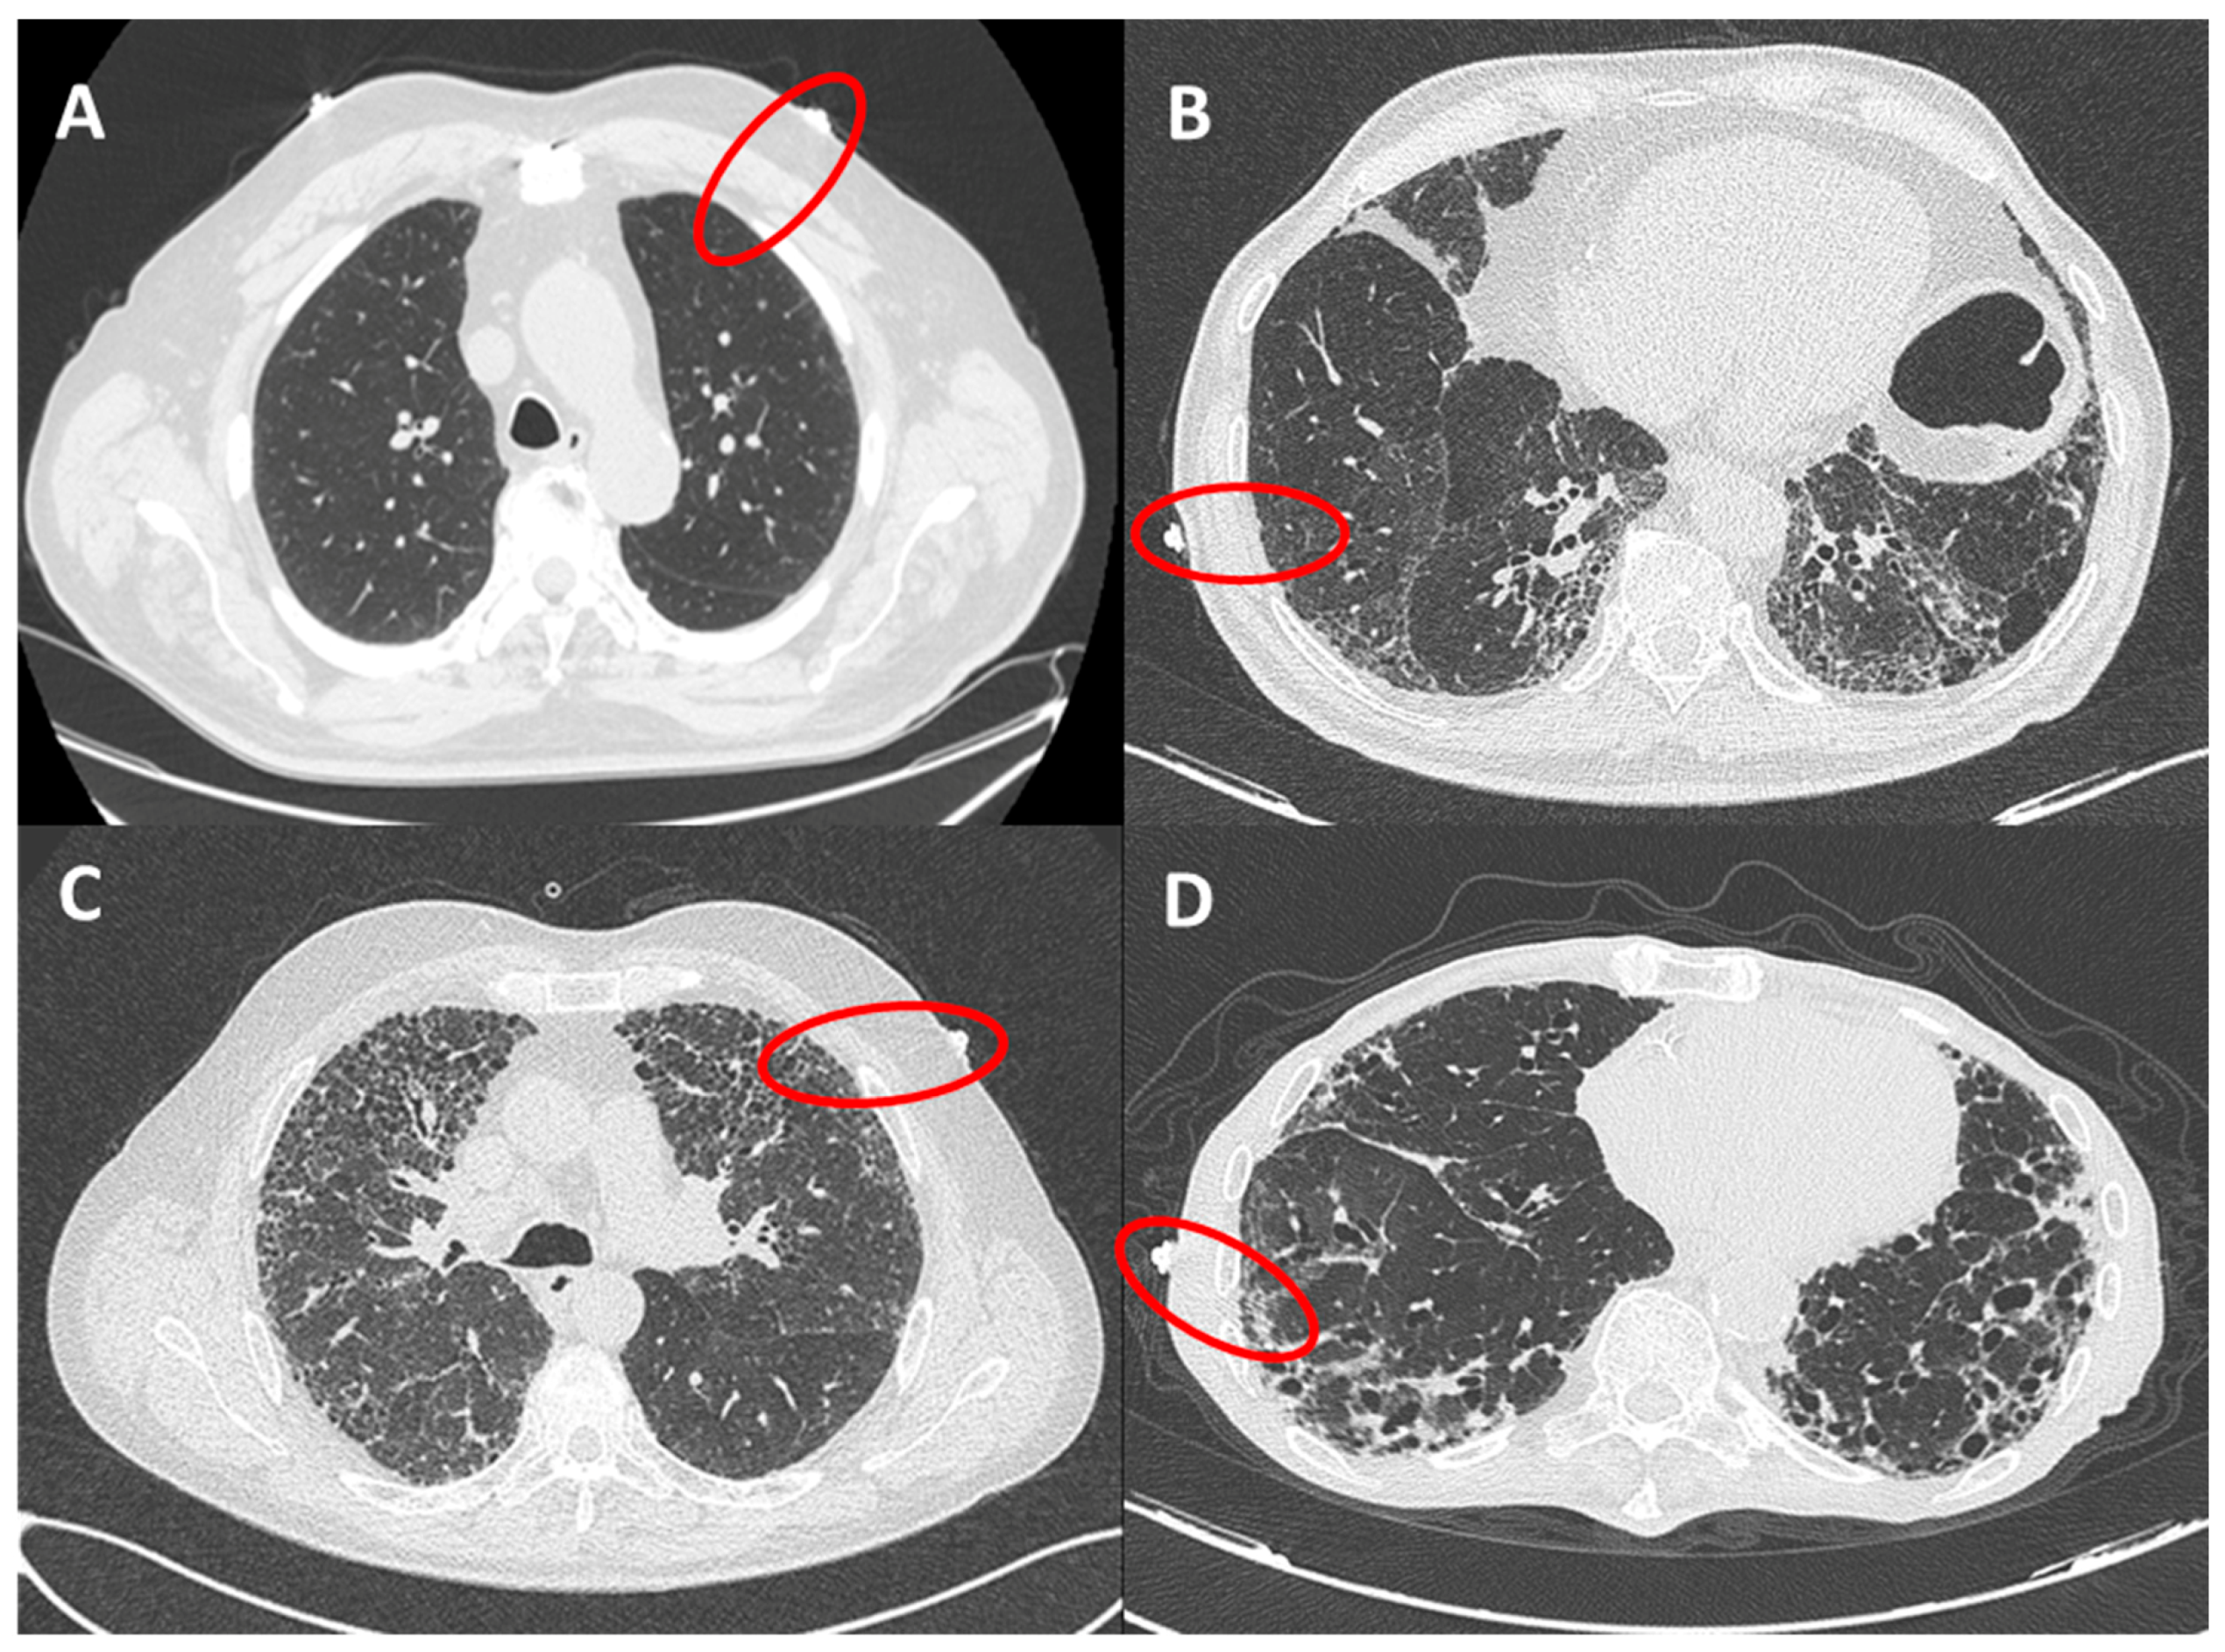

2.2. Chest HRCT Scans